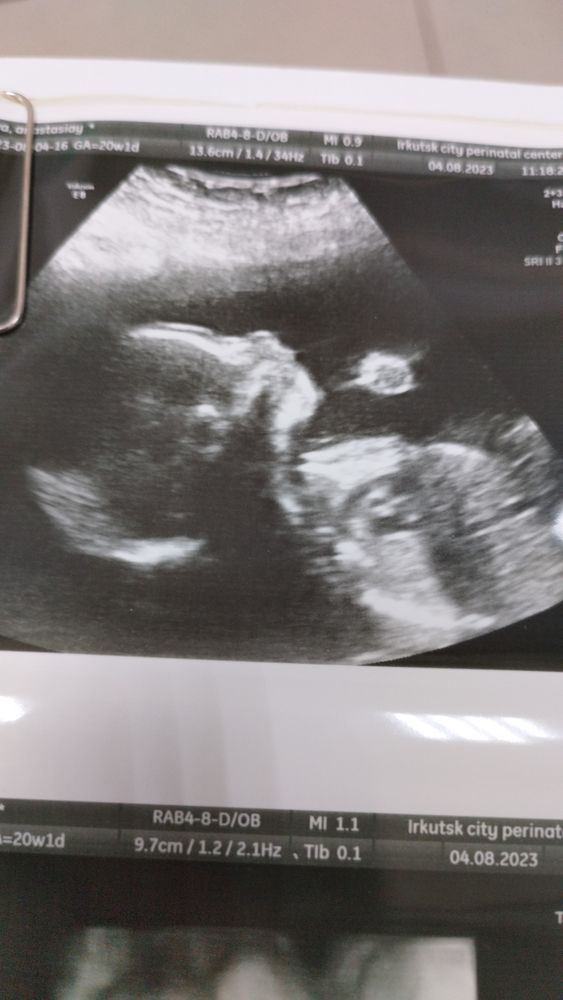

2 скрининг

Привет девочки сегодня сходила на 2 скрининг😊. Наконец закрашиваю кружочек увидела свою девочку😍😍😍 красавица наша😘. Сказали что все отлично ребеночек развивается согласно своему сроку. Правда малышка на УЗИ все пальчик сосала, меня спросили вы кушали утром? Говорю нет меня укачивает именно утром в транспорте. В ответ сказали ребенок голодный пальчик сосет.... После больницы сразу кушать пошли😋 Планировали мальчика конечно, но какая разница кто будет главное что бы здоровенький был☺☺☺. Так что будет у нас голубоглазая блондинка-принцесса👸. Продолжаем кайфовать и ждать встречи😍